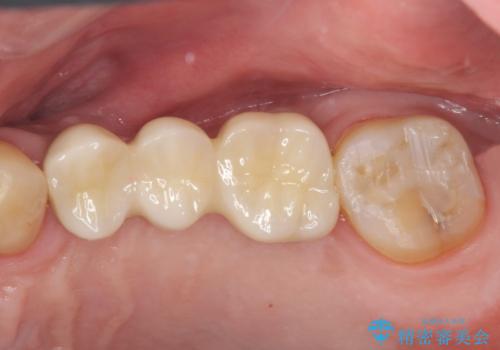

咬合平面を揃え、早期接触・干渉を防ぐ補綴治療

今回、左下6は頬側歯頚部に虫歯があり圧下を行ったことからクラウンにより補綴を行いました。